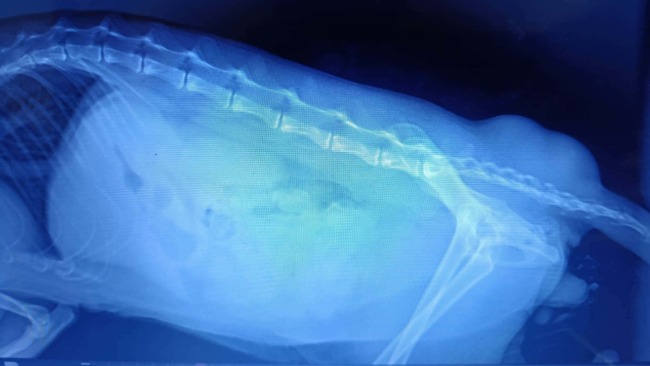

Przyczyn niedowładu mogło być wiele, więc wykonaliśmy wszystkie niezbędne badania - wykluczyliśmy Toxoplazmozę, wykonaliśmy badania krwi, sprawdziliśmy kotka też pod kątem FIP. Kluczowa okazała się diagnostyka obrazowa - zdjęcie RTG które wykazało dwa duże ropnie przy kręgosłupie, w okolicy ogona, uciskające na nerwy i uniemożliwiające mu chodzenie. Ropnie zostały dokładnie oczyszczone, a rana już po kilku dniach zaczęła pięknie się goić.